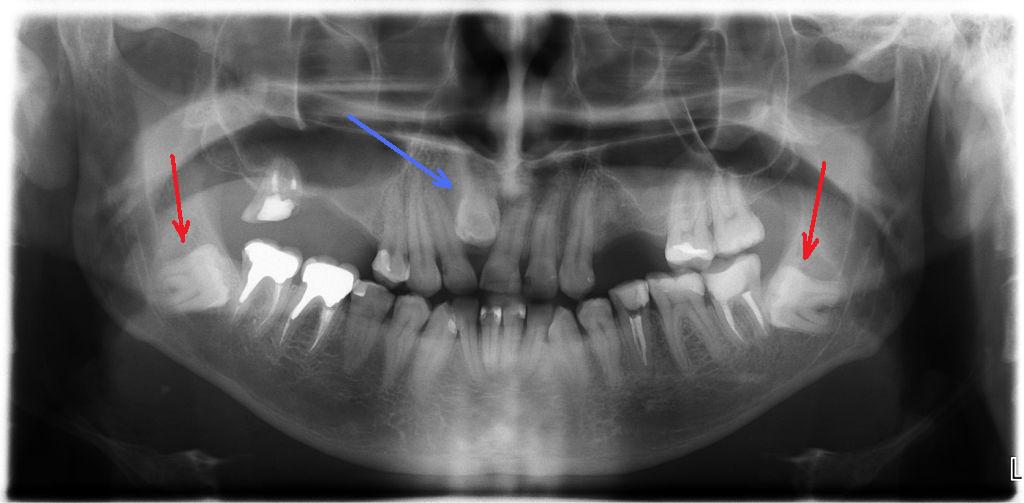

Диагностика и анализ изображений

ИИ может анализировать рентгеновские снимки‚ компьютерные томограммы (КТ) и фотографии зубов с невероятной точностью. Он способен выявлять мельчайшие детали‚ которые могут быть незаметны человеческому глазу‚ такие как:

- Скрытые кариозные поражения.

- Аномалии развития зубов.

- Проблемы с височно-нижнечелюстным суставом (ВНЧС).

- Неправильное положение зубов и челюстей.

Это позволяет врачам ставить более точные диагнозы и разрабатывать более эффективные планы лечения.